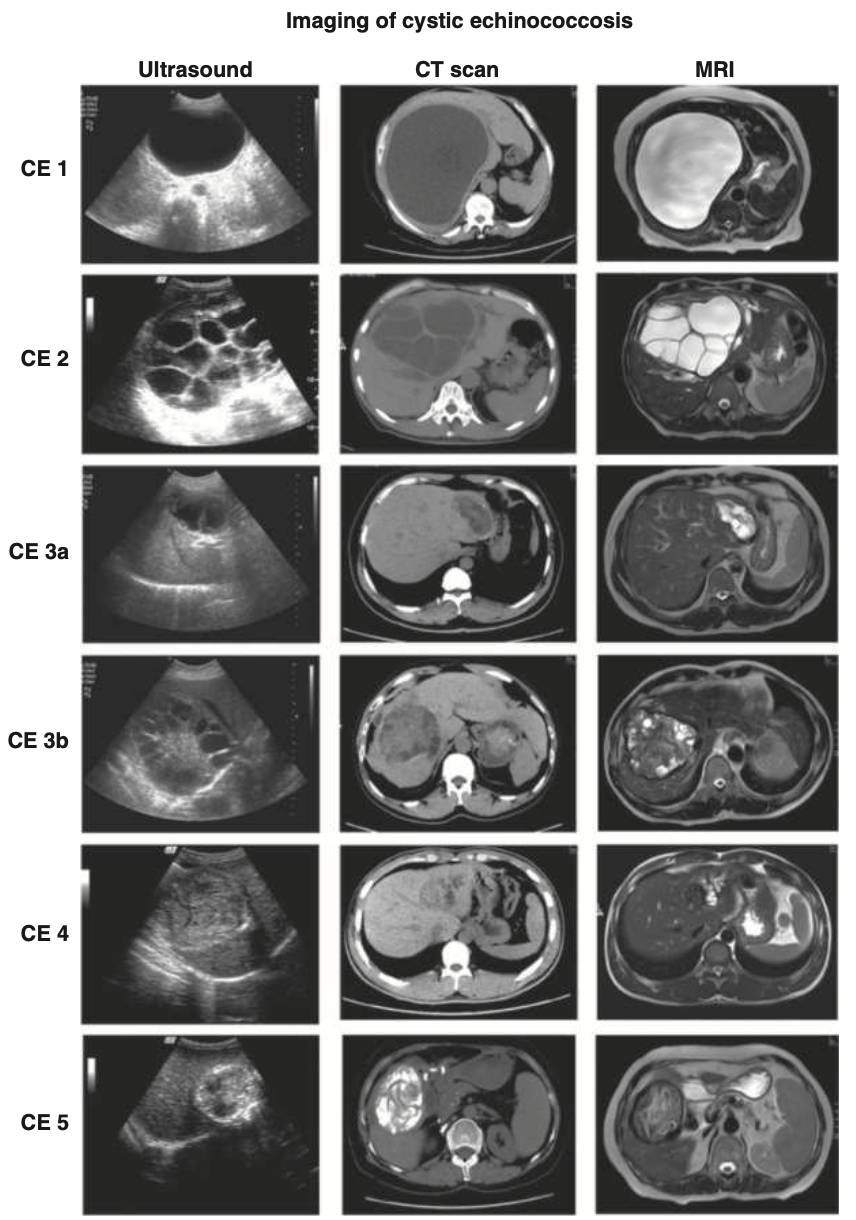

• 진단적 영상 검사 (Diagnostic Imaging)

• Ultrasound (초음파)

• CT scan

• MRI

• 낭종 분류 및 진단 (WHO-IWGE Classification)

• Active Cysts (Viable, 활성 낭종)

• Type CL: Cystic lesion with no visible cyst wall (낭종벽이 보이지 않는 낭성 병변)

• Type CE1: Visible cyst wall and internal echoes (snowflake sign) (낭종벽이 보이고 내부 에코 관찰)

• Type CE2: Visible cyst wall and internal septation (낭종벽과 내부 격막 관찰)

• Transitional Cysts (이행기 낭종)

• Type CE3a: Detached laminar membranes (분리된 층판 막)

• Type CE3b: Partially collapsed (부분적으로 찌그러짐)

• Inactive Cysts (Non-viable, 비활성 낭종)

• Type CE4: Nonhomogeneous mass (불균질한 종괴)

• Type CE5: Cyst with a thick calcified wall (두꺼운 석회화 벽을 가진 낭종)